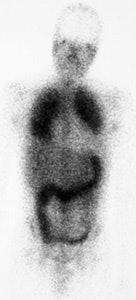

PCP pneumonia: This is a case of PCP pneumonia in an HIV patient with grade 4 tracer accumulation int he lungs (Note the associated colitis) |